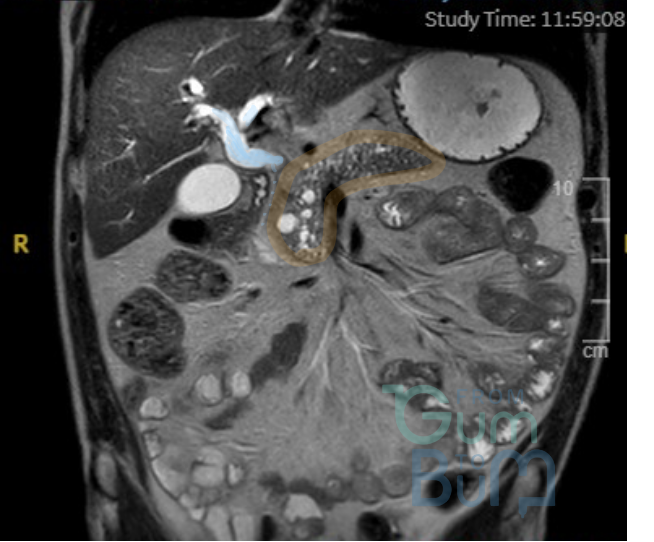

Male 60 yo, presented with dull aching intermittent pain in RUQ for 6 weeks. No fever or diarrhoea. Liver blood test showed ALT of 70 U/L, ALP 150 U/L, rest normal.  FBC showed neutrophilia.

Patient is retired for the last 5 years but used to own a dog rescue shelter. Drinks in excess about 25 units a week since retired. AFP and Ca 19,9 were normal. Serology for Entamoeba histolytica and Echinococcus were equivocal.

Hydatid cyst type II: central cyst with daughter cyst(s). 10% can be seronegative. Key is contact with possible animal hosts (Dog or sheep), incubation period is often years.Amebiasis usually has a preceding history of diarrhoea and fecal-oral transmission. Albendazole 400 mg BD 4 weeks and given cyst is >5cm, consider PAIR therapy. Repeat serology (fluid aspiration has risk of rupture/ anaphylaxis (too risky just for diagnosis)